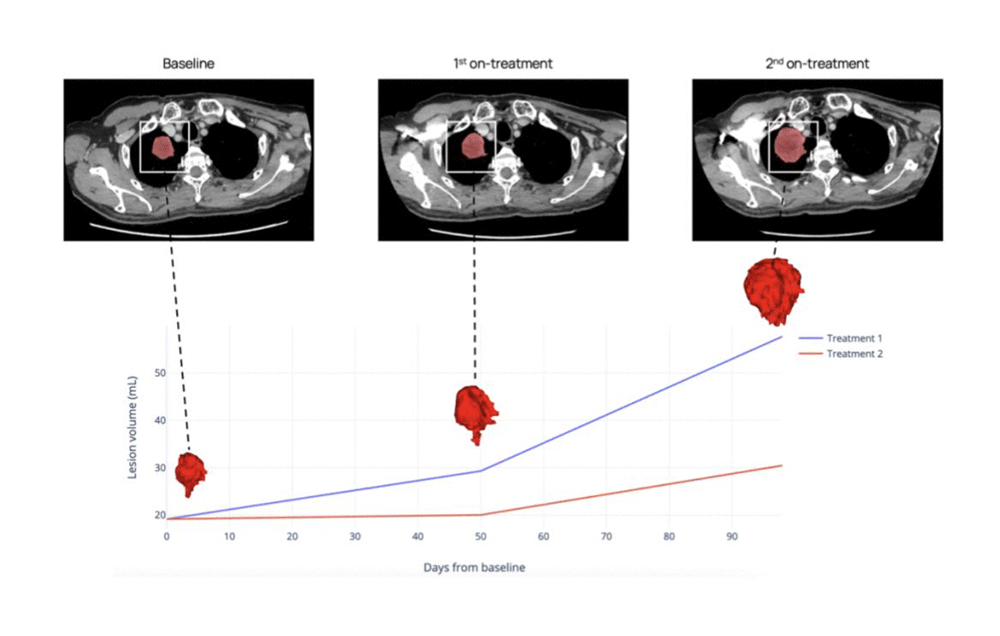

3. Tumor growth kinetics

Retrospective assessment and predictive simulations for individual lesions and tumor burden evolution provides insights into tumor evolution under multiple treatment arms. This capability allows researchers to model and compare treatment outcomes with unprecedented precision.

CT scans of a patient with advanced NSCLC showing target lesion evolution at three time points. This conceptual simulation illustrates how tumor growth kinetics and delta-radiomics can be assessed across treatment regimens. Not based on an actual predictive model.